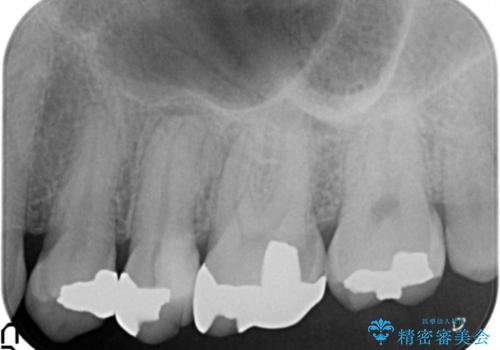

30代女性 ミゼラブルな前歯の陥没を再生する①1次手術による骨造成

- 治療計画

- 他院にて前歯を抜歯され、その後の組織の吸収によりシビアな欠損を伴う状態であった

→2度の手術により失われた骨・および軟組織の再生を図り、最終的にセラミックにて修復を終えた

1次骨造成

1次手術は大きく失われた骨の回復をイニシアティブとして行いました。チタンメッシュは露出や撤去必須などのデメリットがありますが、大規模な骨造成においてはハウジングという観点で圧倒的な安心感があります。

少しでも多くボリュームを増やすことと、骨造成部位の保護という意味で、メッシュとメンブレンを、さらに結合組織で覆うという術式をとりました。単純に結合組織を持ってくると血流の条件を難しくしてしまうため、組織を完全に切り離さず、有茎弁の状態で翻転させ移植しています。